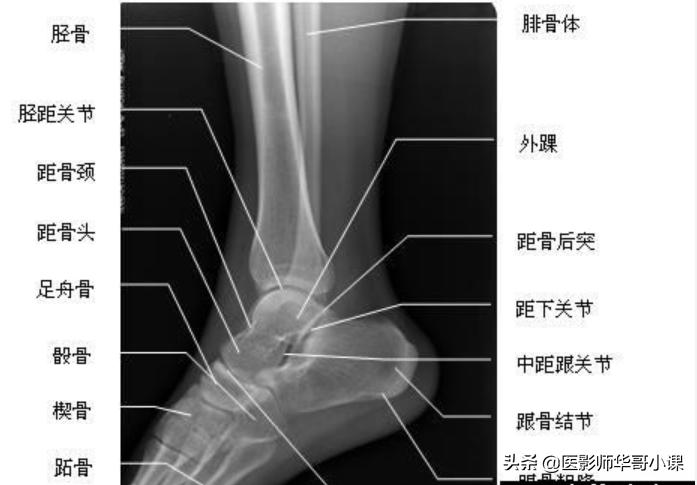

踝关节侧位解剖

医影师:很详细的解剖哦,就知道那个地方叫啥了,踝关节很多结构组成的呢。